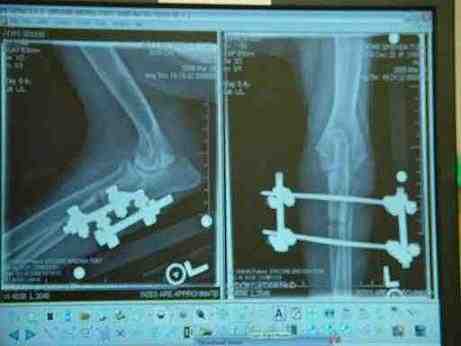

Surgery: On March 17th Toby was placed under general anesthesia for elbow arthroscopy and an ulnar ostectomy. Upon entering the elbow joint, Toby was found to have a fragmented coronoid process. No other abnormalities we found in the elbow. Afterwards an incision was made along the ulna and a section of the ulna was removed. A motorized external fixator was applied to the ulna using two pins. Toby under went numerous procedures where the external fixator was tightened to bring the bone down to joint the other section. This has enabled his joint to fall back in place. Dr. Chambers said that this abnormal growth in Toby was exactly the opposite of what usually happens in these cases and so they used his case to teach the procedure. He said, that most of them might never in their lifetime see this type problem again. He had the surgeon that invented the external device come in and apply it after they prepared the bone for it. Toby will wear this 4 weeks and then be put back to sleep to remove it. Dr. Chambers said, he could not say for sure if his problem was genetic or from an injury.

Toby's post-op x-rays